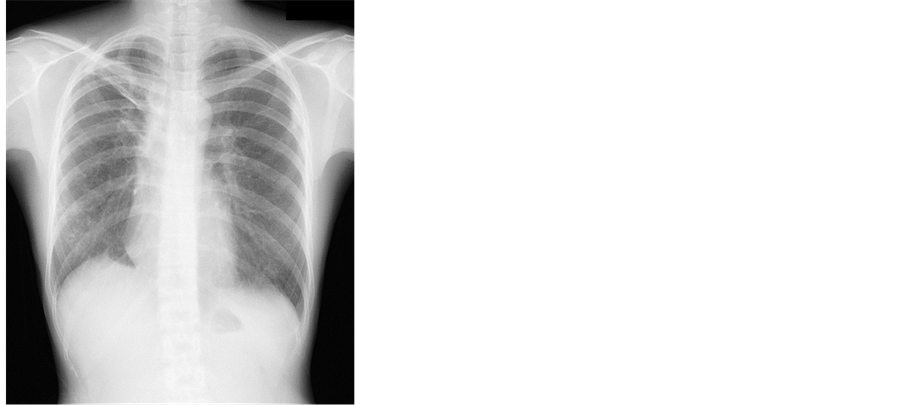

Case 2: A 33-year-old woman visited our hospital complaining of productive cough and general fatigue. She had no underlying diseases and no smoking history. There were no abnormal physical findings on admission. There were no abnormal laboratory findings except for the elevation of C-reactive protein (CRP 0.34 mg/dl, normal range: <0.30 mg/dl). Although TST was not performed, QFT-G was negative (<0.05 IU/ml). Chest radiographs showed linear shadows in the right upper lung field and cavity lesions in the right upper and lower lung fields (Figure 3). Chest CT showed several cavities surrounding the infiltration shadow and satellite lesions with bronchiectasis in the right upper and lower lobes (Figure 4). The culture of expectorated sputum generated

Figure 3. Chest radiographs showed linear shadows in the right upper filed and cavity lesions in the right upper and lower lung fields.